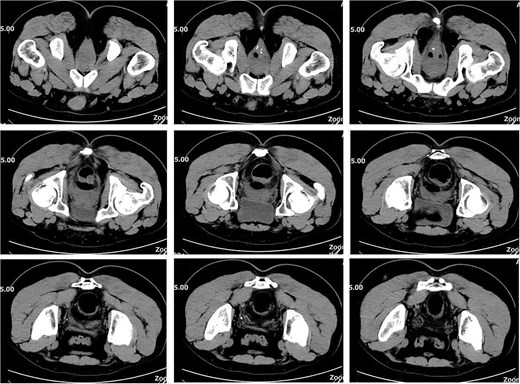

On postoperative Day 7, the patient developed a fever (38.5°C) and mild lower abdominal discomfort. Laboratory tests revealed leukocytosis (white blood cell count: 16.06 × 109/l, neutrophil percentage: 89.1%). A pelvic computed tomography (CT) scan suggested cystitis (Fig. 1). Anti-infective therapy with intravenous cefoperazone sodium and sulbactam sodium was initiated. The patient’s vital signs, complete blood count, and temperature were closely monitored.